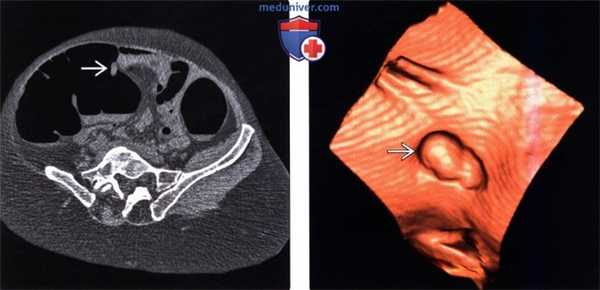

(Слева) На рентгенограмме толстой кишки с двойным контрастированием визуализируется множественные мелкие полипы, в основном 2-5 мм. Количество полипов толстой кишки при семейном полипозе может варьировать от нескольких сотен до тысяч, как в этом случае.

(Справа) На аксиальной КТ с контрастным усилением у мужчины 26 лет, который не предоставил информацию о заболеваниях раком толстой кишки среди его ближайших родственников, визуализируются множественные метастазы первичного рака толстой кишки в печень. (Слева) На аксиальной КТ у этого же пациента визуализируется одно из трех образований толстой кишки, каждое из которых является запущенным раком, прорастающим стенку кишки с наличием поражения регионарных лимфоузлов и метастазами в печень.

(Слева) На аксиальной КТ с контрастным усилением у этого же пациента (с ректальным кровотечением и снижением веса тела) визуализируется образование прямой кишки больших размеров, распространяющееся за пределы ее стенки; определяется инфильтрация параректальной жировой клетчатки и метастазы в регионарные лимфоузлы. (Слева) На рентгенограмме верхних отделов ЖКТ визуализируется желудок, целиком покрытый мелкими полипами, одинаковыми по виду. Несмотря на то, что эти полипы напоминают гиперпластические по своим лучевым признакам, в действительности пациент страдает семейным полипозом с наличием аденоматозных полипов, которые обладают способностью к злокачественной трансформации.

(Справа) На рентгенограмме верхних отделов ЖКТ у пациента с семейным полипозом и синдромом Гарднера визуализируются несколько аденоматозных полипов в двенадцатиперстной кишке.